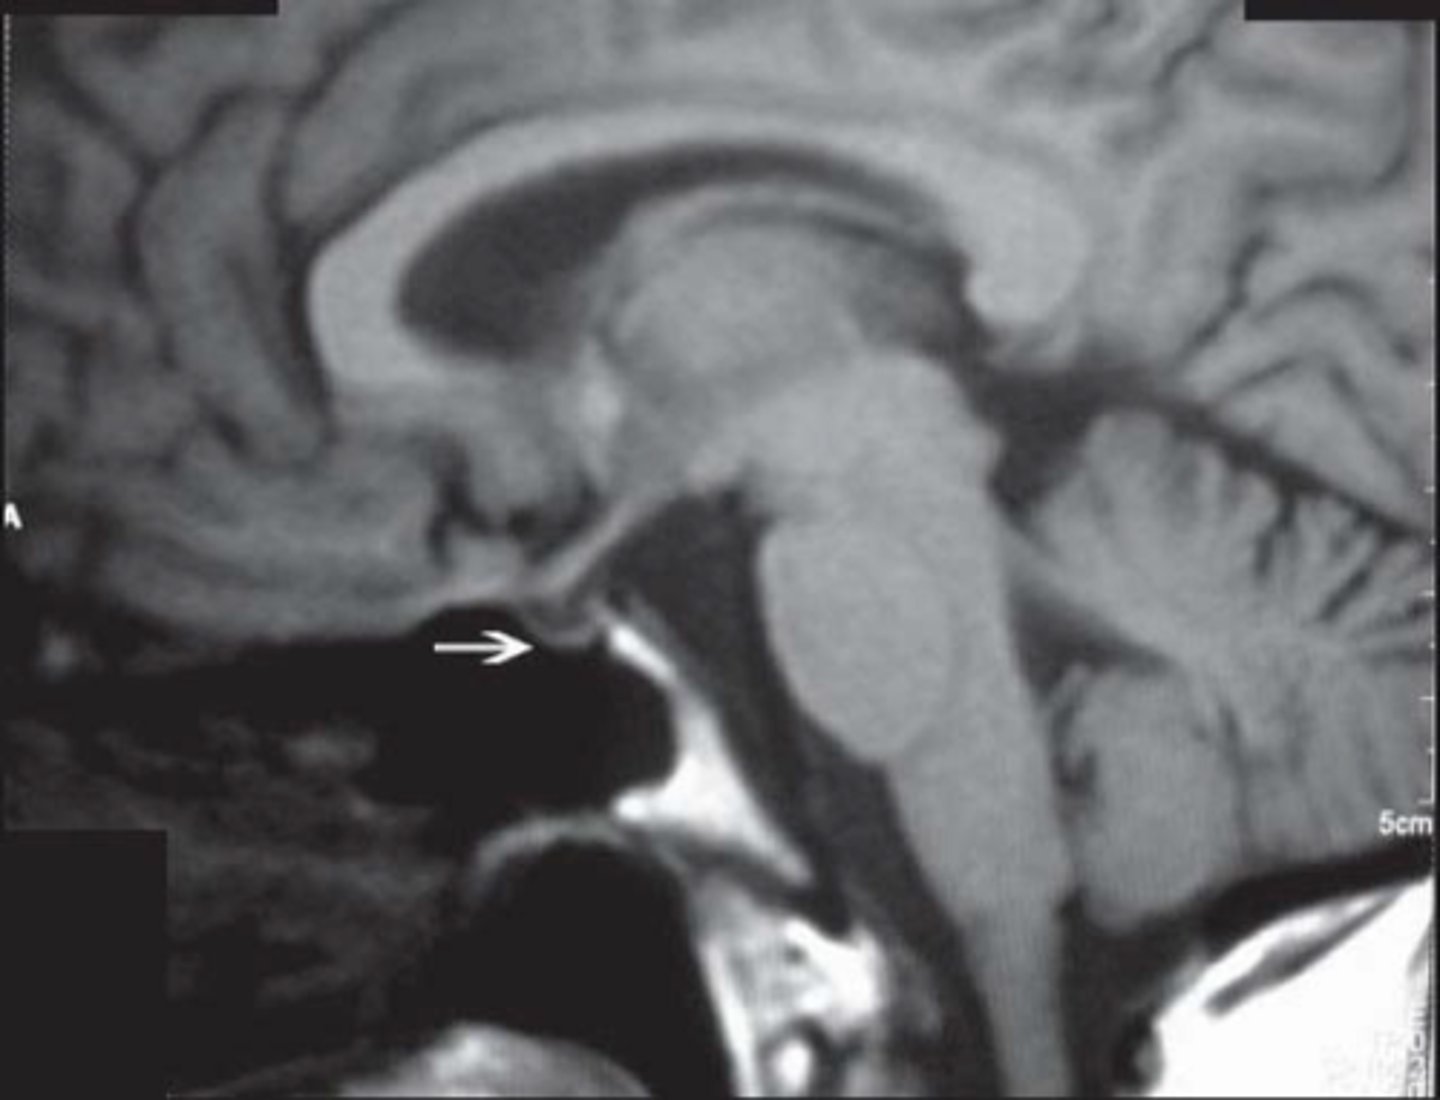

Multiple sclerosis

Type IV hypersensitivity

Dx: Oligoclonal IgG bands and periventricular plaques on MRI